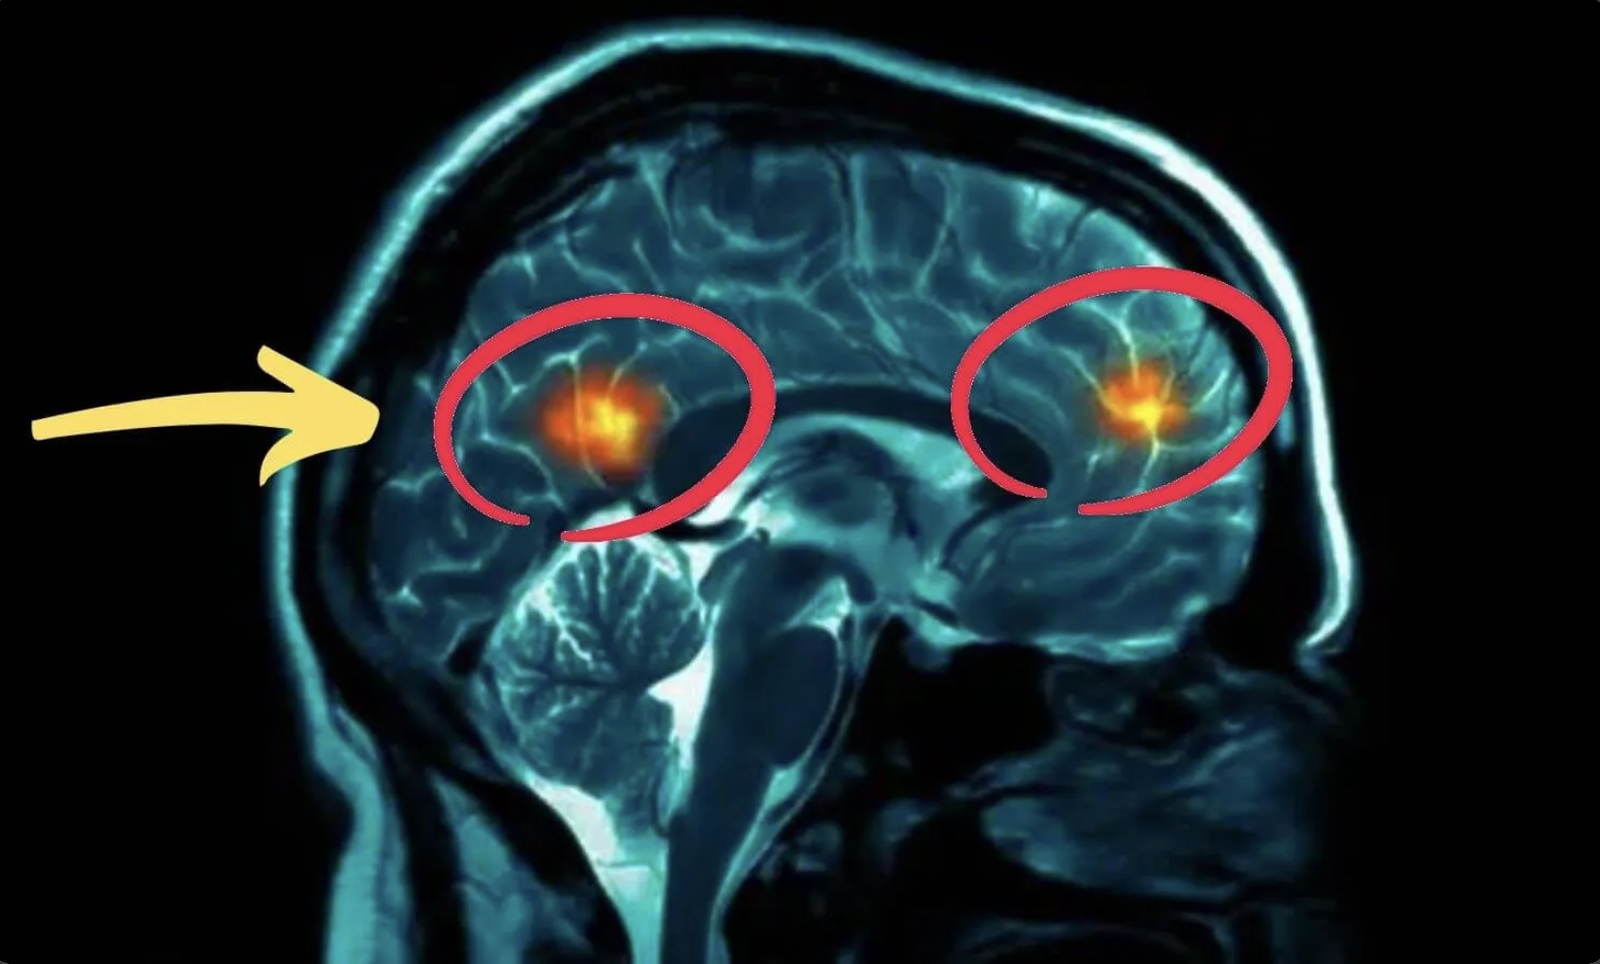

But newer insights suggest that for many adults, vertigo can also be linked to a balance signal that can get “thrown off” over time.

When that signal stays “off,” dizziness and unsteadiness can feel unpredictable, no matter what you try.

There’s a simple daily action designed to support this balance signal, and it takes about 10 seconds a day.

the simple balance trigger most people overlook